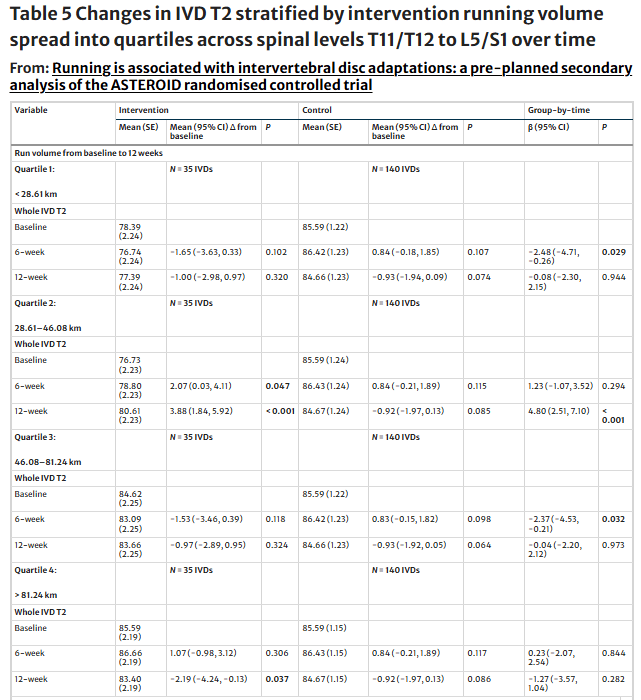

- Факторы вмешательства: Кумулятивный объем бега, средняя скорость бега и доминирующая поверхность для бега (трава, гравий, тротуар или тропа) оценивались с помощью бесплатного приложения Runkeeper. Совокупный объем бега и средняя скорость бега были распределены по квартилям IVD для анализа от исходного уровня до 12 недель. Все модераторы вмешательства сравнивались с контрольной выборкой.

Если рассматривать факторы вмешательства, то суммарные объемы бега от 28,6 до 46,1 км положительно влияли на межгрупповой показатель IVD T2 в течение 12 недель. В то время как суммарные объемы бега менее 28,6 км или от 46,1 до 81,2 км отрицательно влияли на межгрупповую динамику IVD T2, однако только в течение шести недель. Объем бега от 6 до 12 недель менее 14,8 км положительно влиял на межгрупповой показатель IVD T2 только через 12 недель.

Вмешательство в виде бега с ходьбой было разработано как консервативное, что привело к широкому разбросу средних скоростей бега (от 4,4 до 11,7 км/ч) и суммарных объемов бега (от 1,8 до 109,8 км). Хотя это дало возможность провести анализ по подгруппам, он отражает высокую вариабельность фактической "дозы" бега.

Объем бега демонстрирует "оптимальную точку": Исходя из текущего анализа, оптимальным будет диапазон 28,6-46,1 км за 12 недель, что составляет примерно 2,4-3,8 км/неделю. Слишком мало или слишком много показали U-образную зависимость между нагрузкой и адаптацией, с отрицательным эффектом, в основном на 6 неделе.